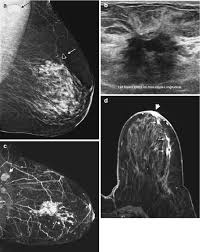

Mri Breast Cancer Detection from breast-cancer.ca Mri of inflammatory breast cancer women's imaging original research. They're often easy to move around (mobile) and may be tender. Inflammatory breast cancer pictures and symptoms Inflammatory breast cancer (ibc) is rare, making up about 2 to 4 percent of breast cancer cases. A small red spot that looks very much like an insect bite or rash can be an early sign of ibc. But not every woman who has been diagnosed with breast cancer needs a breast mri. The features of a malignant breast condition on mri scan are often to do with the outer irregular borders of a lesion. Clinically, inflammatory breast cancer mimics mastitis.

The features of a malignant breast condition on mri scan are often to do with the outer irregular borders of a lesion. Inflammatory breast cancer affects breast tissue and can appear unusually dimpled or thick. Absence of lump or breast mass in a patient suffering from an inflammatory skin condition of the breast, suggests the presence of skin or subcutaneous inflammatory condition caused by either infection or inflammatory breast cancer. The skin looks like the skin of an orange, and may be discolored with painful and itchy breast. The breast is enlarged (often of relatively short onset), indurated, erythematous, warm, and may be tender and painful. But not every woman who has been diagnosed with breast cancer needs a breast mri. What does breast cancer look like on a mammogram? A lump in the breast. Breast mri is sometimes used in women who already have been diagnosed with breast cancer, to help measure the size of the cancer, look for other tumors in the breast, and to check for tumors in the opposite breast. Most cases are invasive ductal carcinomas, which develop in the cells lining the milk ducts and spread throughout the breast. The breast can also be painful in inflammatory breast cancer, but this is not always the case. Evaluating the impact of preoperative breast magnetic resonance imaging on the surgical management of newly diagnosed breast cancers. When the cancer grows into the rest of the body through the blood vessels and lymph vessels, breast cancer spreads.

Ovarian Cancer Metastatic To The Breast Presenting As Inflammatory Breast Cancer A Case Report And Literature Review from www.jcancer.org This type of cancer also changes the appearance of your breasts. What does breast cancer look like on a mammogram? Inflammatory breast cancer develops when cancer cells block the lymph vessels in the skin of the breast. However, these signs and symptoms are most often associated with benign breast conditions. Breast infections can cause redness and swelling. The skin looks like the skin of an orange, and may be discolored with painful and itchy breast. Breast mri images are combined, using a computer, to create detailed pictures. Bilimoria ky, cambic a, hansen nm, bethke kp.

Inflammatory breast cancer is an an aggressive and fast growing breast cancer in which cancer cells infiltrate the skin and lymph vessels of the breast. They're often easy to move around (mobile) and may be tender. Ibc symptoms are caused by cancer cells blocking lymph vessels in the skin causing the breast to look inflamed. symptoms include breast swelling, purple or red color of the skin, and dimpling or thickening of the skin of the breast so that it may look and feel like an orange peel. Unlike traditional forms of breast cancer, inflammatory breast cancers do not develop unusual lumps within the affected breast. The skin is thickened and edematous, classically with a peau d'orange appearance. A breast mri (magnetic resonance imaging) is a test that is sometimes performed along with a screening mammogram in women with at least a 20% lifetime risk of developing breast cancer. What does breast cancer look like on a mammogram? Mri of breast can help breast cancer diagnosis. Inflammatory breast cancer inflammatory breast cancer is a rare type of breast cancer that develops rapidly, making the affected breast red, swollen and tender. A rash isn't the only visual symptom of inflammatory breast cancer. Inflammatory breast cancer (ibc) is rare, making up about 2 to 4 percent of breast cancer cases. Inflammatory breast cancer pictures and symptoms The skin looks like the skin of an orange, and may be discolored with painful and itchy breast.

It blocks the lymph vessels in the skin of your breast. They're often easy to move around (mobile) and may be tender. When the cancer grows into the rest of the body through the blood vessels and lymph vessels, breast cancer spreads. Breast lesions and chest wall abnormalities 8. Pitting, thickening, or dimpling of skin on the breast, so that it looks like an orange peel, a condition called peau d'orange. Most cases are invasive ductal carcinomas, which develop in the cells lining the milk ducts and spread throughout the breast. To help determine the extent of breast cancer: There may or may not be an underlying palpable mass. Mri of breast can help breast cancer diagnosis. Inflammatory breast cancer pictures show a red and/or swollen breast that appears inflamed. A breast mri usually is performed after you have a. J natl compr canc netw. If these tests don't answer the quest.